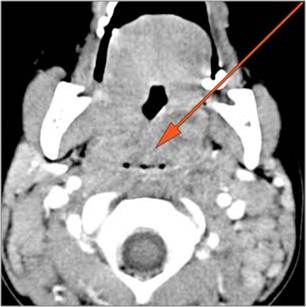

Retropharyngeal Lymph Nodes

There is reactive cervical lymphadenopathy. [Yes/No]

There is suppurative cervical lymphadenopathy. [Yes/No]